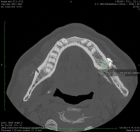

Sagittal split osteotomy (SSO) of the mandible is still an important part of orthognathic surgery, but “bad split” fractures that happen during the surgery are still a big problem. This report describes a rare case of bilateral bad split associated with highly compact mandibular bone (D1–D2 type) in a 53-year-old male undergoing mandibular advancement. The bone was too hard for the piezoelectric and rotary tools to work, and there was very little bleeding. This caused fractures in the cortex and lingual. Postoperative computed tomography confirmed the presence of highly dense bone, correlated with delayed healing and recurrence. Consistent pre-surgical CT scanning for an assessment of the density of the mandibular bone can provide essential information about the potential risk of the osteotomy procedure in the patient. Performing a careful bone quality and density examination pre-operatively will allow the surgeons to select the most appropriate instruments and surgical techniques that will fit the patient’s individual anatomy. Such a point escalates to being very significant when dealing with the geriatric population, as bone density increase can not only alter the fracture behavior but also the recovery process during and after surgery. The inclusion of regular CT-based bone density evaluations into the preoperative routine not only facilitates the anticipation of surgical difficulties but also results in safer and more efficient osteotomies.

Figure 2